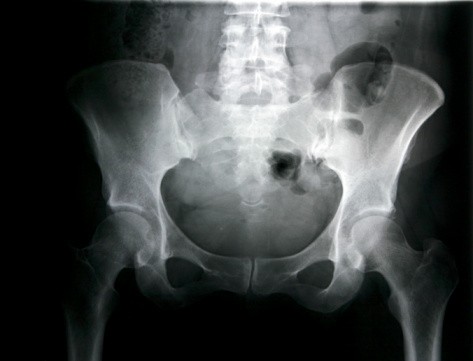

Namun sederhananya, Ketua Bidang IPTEK KONI DKI Jakarta, dr Arie Sutopo, SpKO, mengungkapkan bahwa cedera selangkangan bisa diartikan dengan adanya gangguan atau nyeri pada ligamen dan otot di sekitar selangkangan ketika digerakkan.

Lantas apa penyebabnya? Bagi dr Michael Triangto, SpKO, ada alasan tertentu mengapa selangkangan sering mengalami cedera, terutama bagi olahragawan. Hal ini dikarenakan selangkangan terdiri atas otot-otot besar, yaitu gracillis, sartorius dan adductor yang paling sering mengalami strain (peregangan).

"Namun bila taraf peregangannya cukup parah, bisa terjadi sprain di mana sudah terjadi robekan pada otot, atau mungkin muscle tear jika kondisinya lebih parah lagi. Rasa sakitnya seperti peradangan hebat," paparnya saat dihubungi dalam kesempatan terpisah.